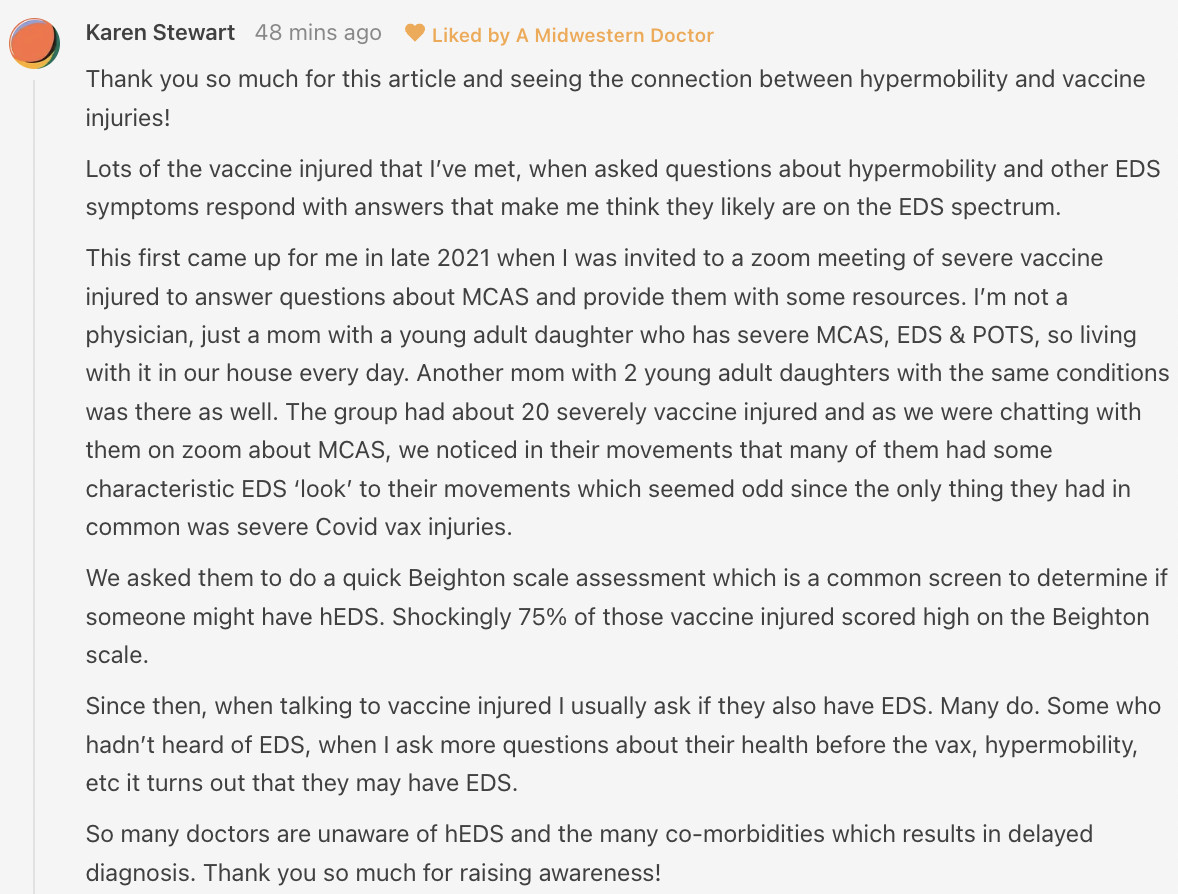

There has been a longstanding observation in the integrative field that ligamentous laxity correlates with a predisposition to vaccine injuries. Likewise, a lot of readers have shared this observation with me after I broached this subject. For example, this comment was left by one reader:

Gardasil caused a variety of debilitating conditions (e.g., constant fatigue, cognitive impairment, a variety of autoimmune conditions and widespread neurologic dysregulation—things also frequently seen after the COVID-19 vaccination). At some point, holistic physicians began noticing patients (particularly women) with existing ligamentous laxity were much more likely to develop Gardasil injuries (and in turn a few researchers proposed genetic variations to account for this).